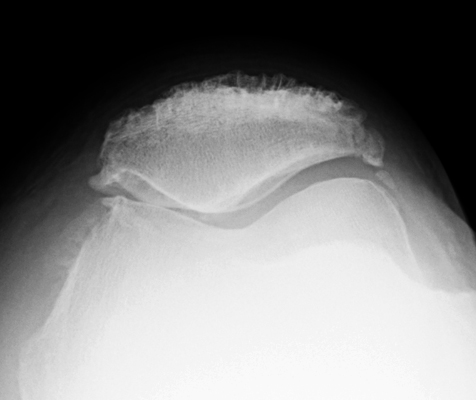

Diagnosis:Enthesopathy Discussion:Enthesopathy of the patella at the attachment of the quadriceps tendon on the axial view of the patella (sunrise view) resemble teeth. References: